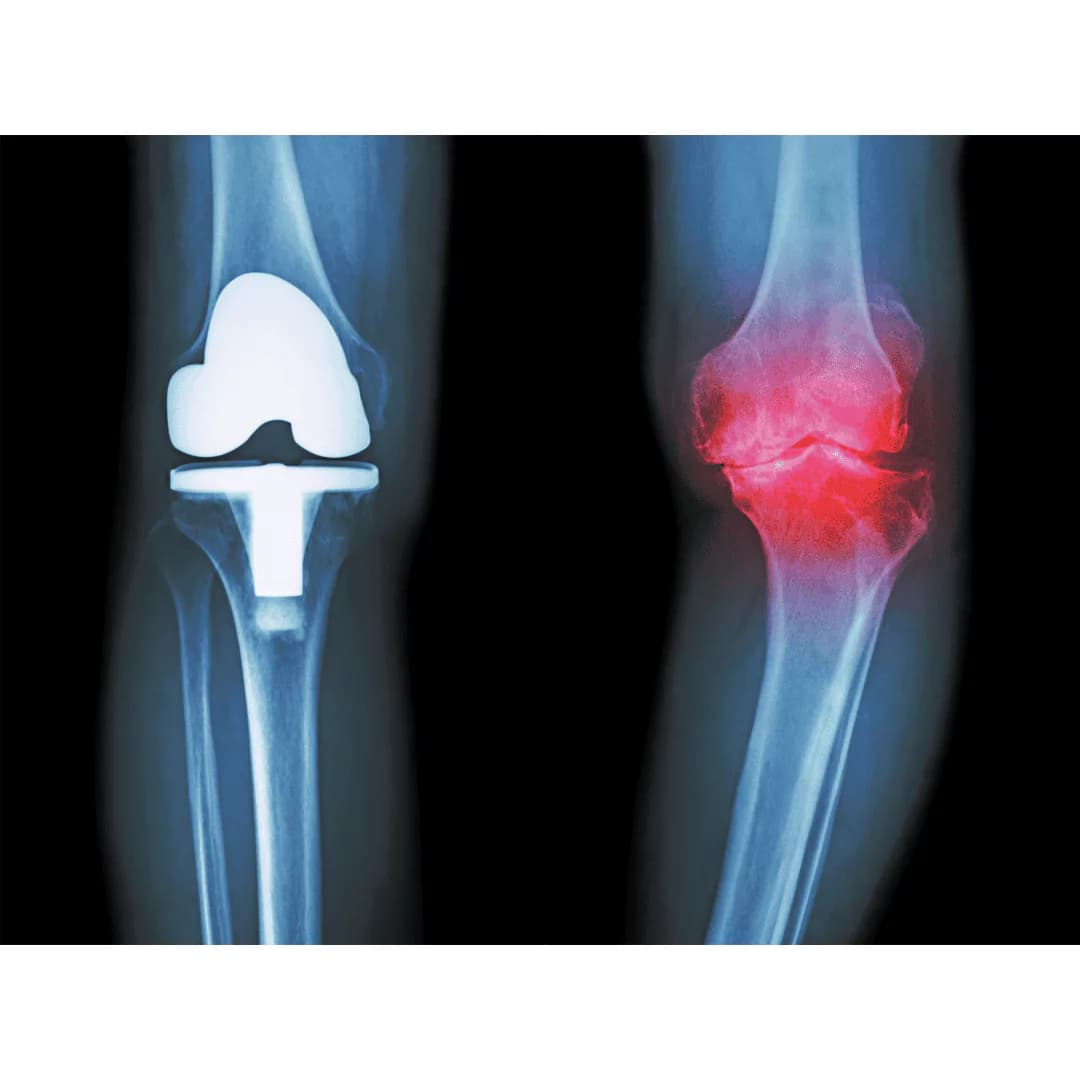

Types of Artificial Knee Joints

- Complete Artificial Joint

- Used in advanced cases of knee cartilage erosion.

- The damaged bone surface is replaced with a high-quality metal or plastic layer.

- Provides the patient with smooth movement after recovery.

- Partial Artificial Joint

- Suitable for cases where erosion is limited to a specific part of the knee.

- Only the damaged part is replaced, preserving healthy tissues.

- Shorter recovery period compared to the complete joint.